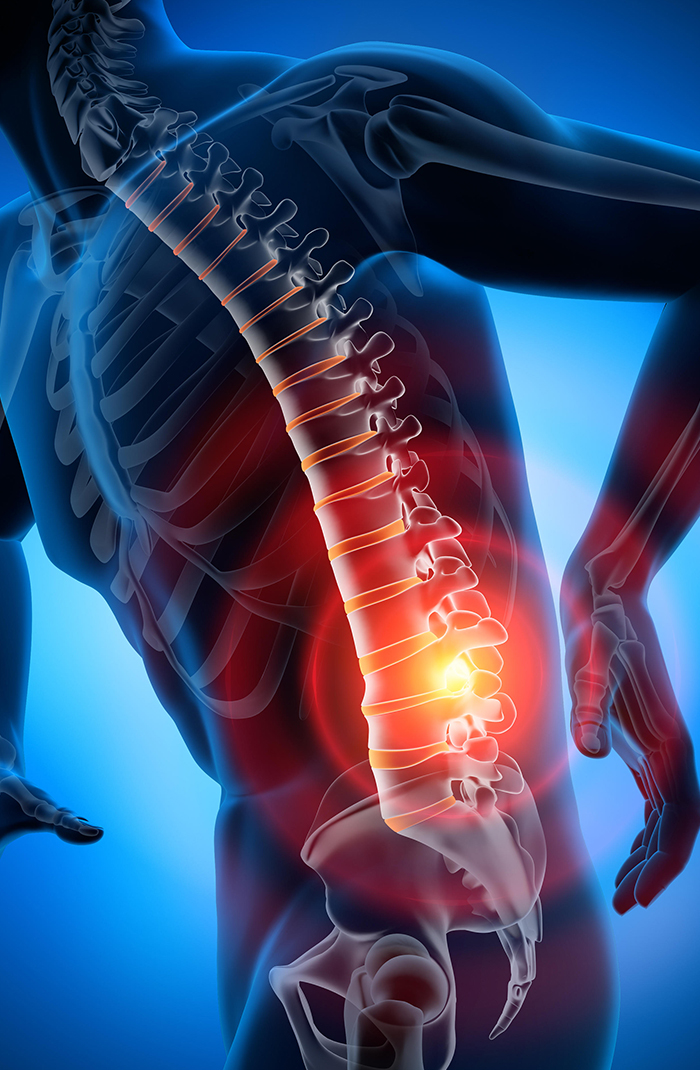

?????? ???????? ???????? ??? ?? ??? ????: ????? ??????.